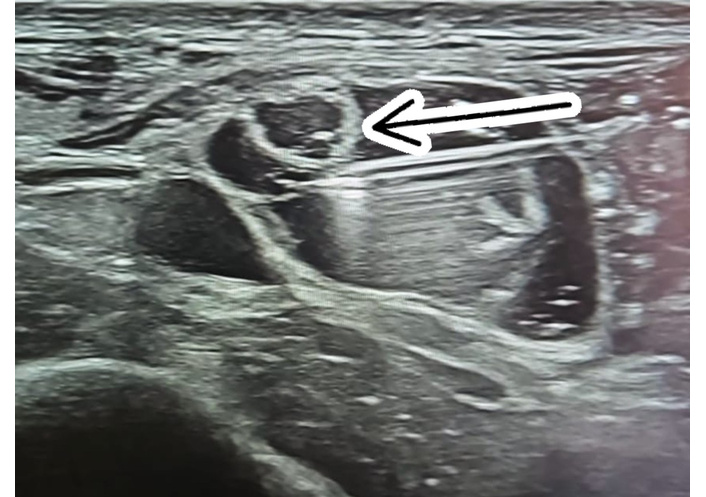

High-frequency ultrasound revealed enlargement and thickening of the affected nerves, along with altered fascicular echotexture. The surrounding fascia appeared thickened with reduced elasticity during probe compression, and nerve glide was notably limited. Several oval or fusiform hypoechoic structures were also observed, consistent with trigger-point-like areas within taut bands. These sonographic findings closely matched the palpable indurations and the patient’s mechanically induced symptoms (Figure 1).

Ultrasound imaging of the medial branch of the superficial peroneal nerve: sclerotic fibrosis, nerve thickening, and fascial changes. (A): Medial branch of the superficial peroneal nerve, with sclerotic fibrosis highlighting a clear passage of the nerve (arrow). (B): Transverse ultrasound at the site of pain, as indicated by the patient, showing the medial branch of the superficial peroneal nerve (arrow). Imaging demonstrates increased cross-sectional area, nerve thickening, altered echotexture, thickening of the overlying fascia, and the presence of fibrosis.